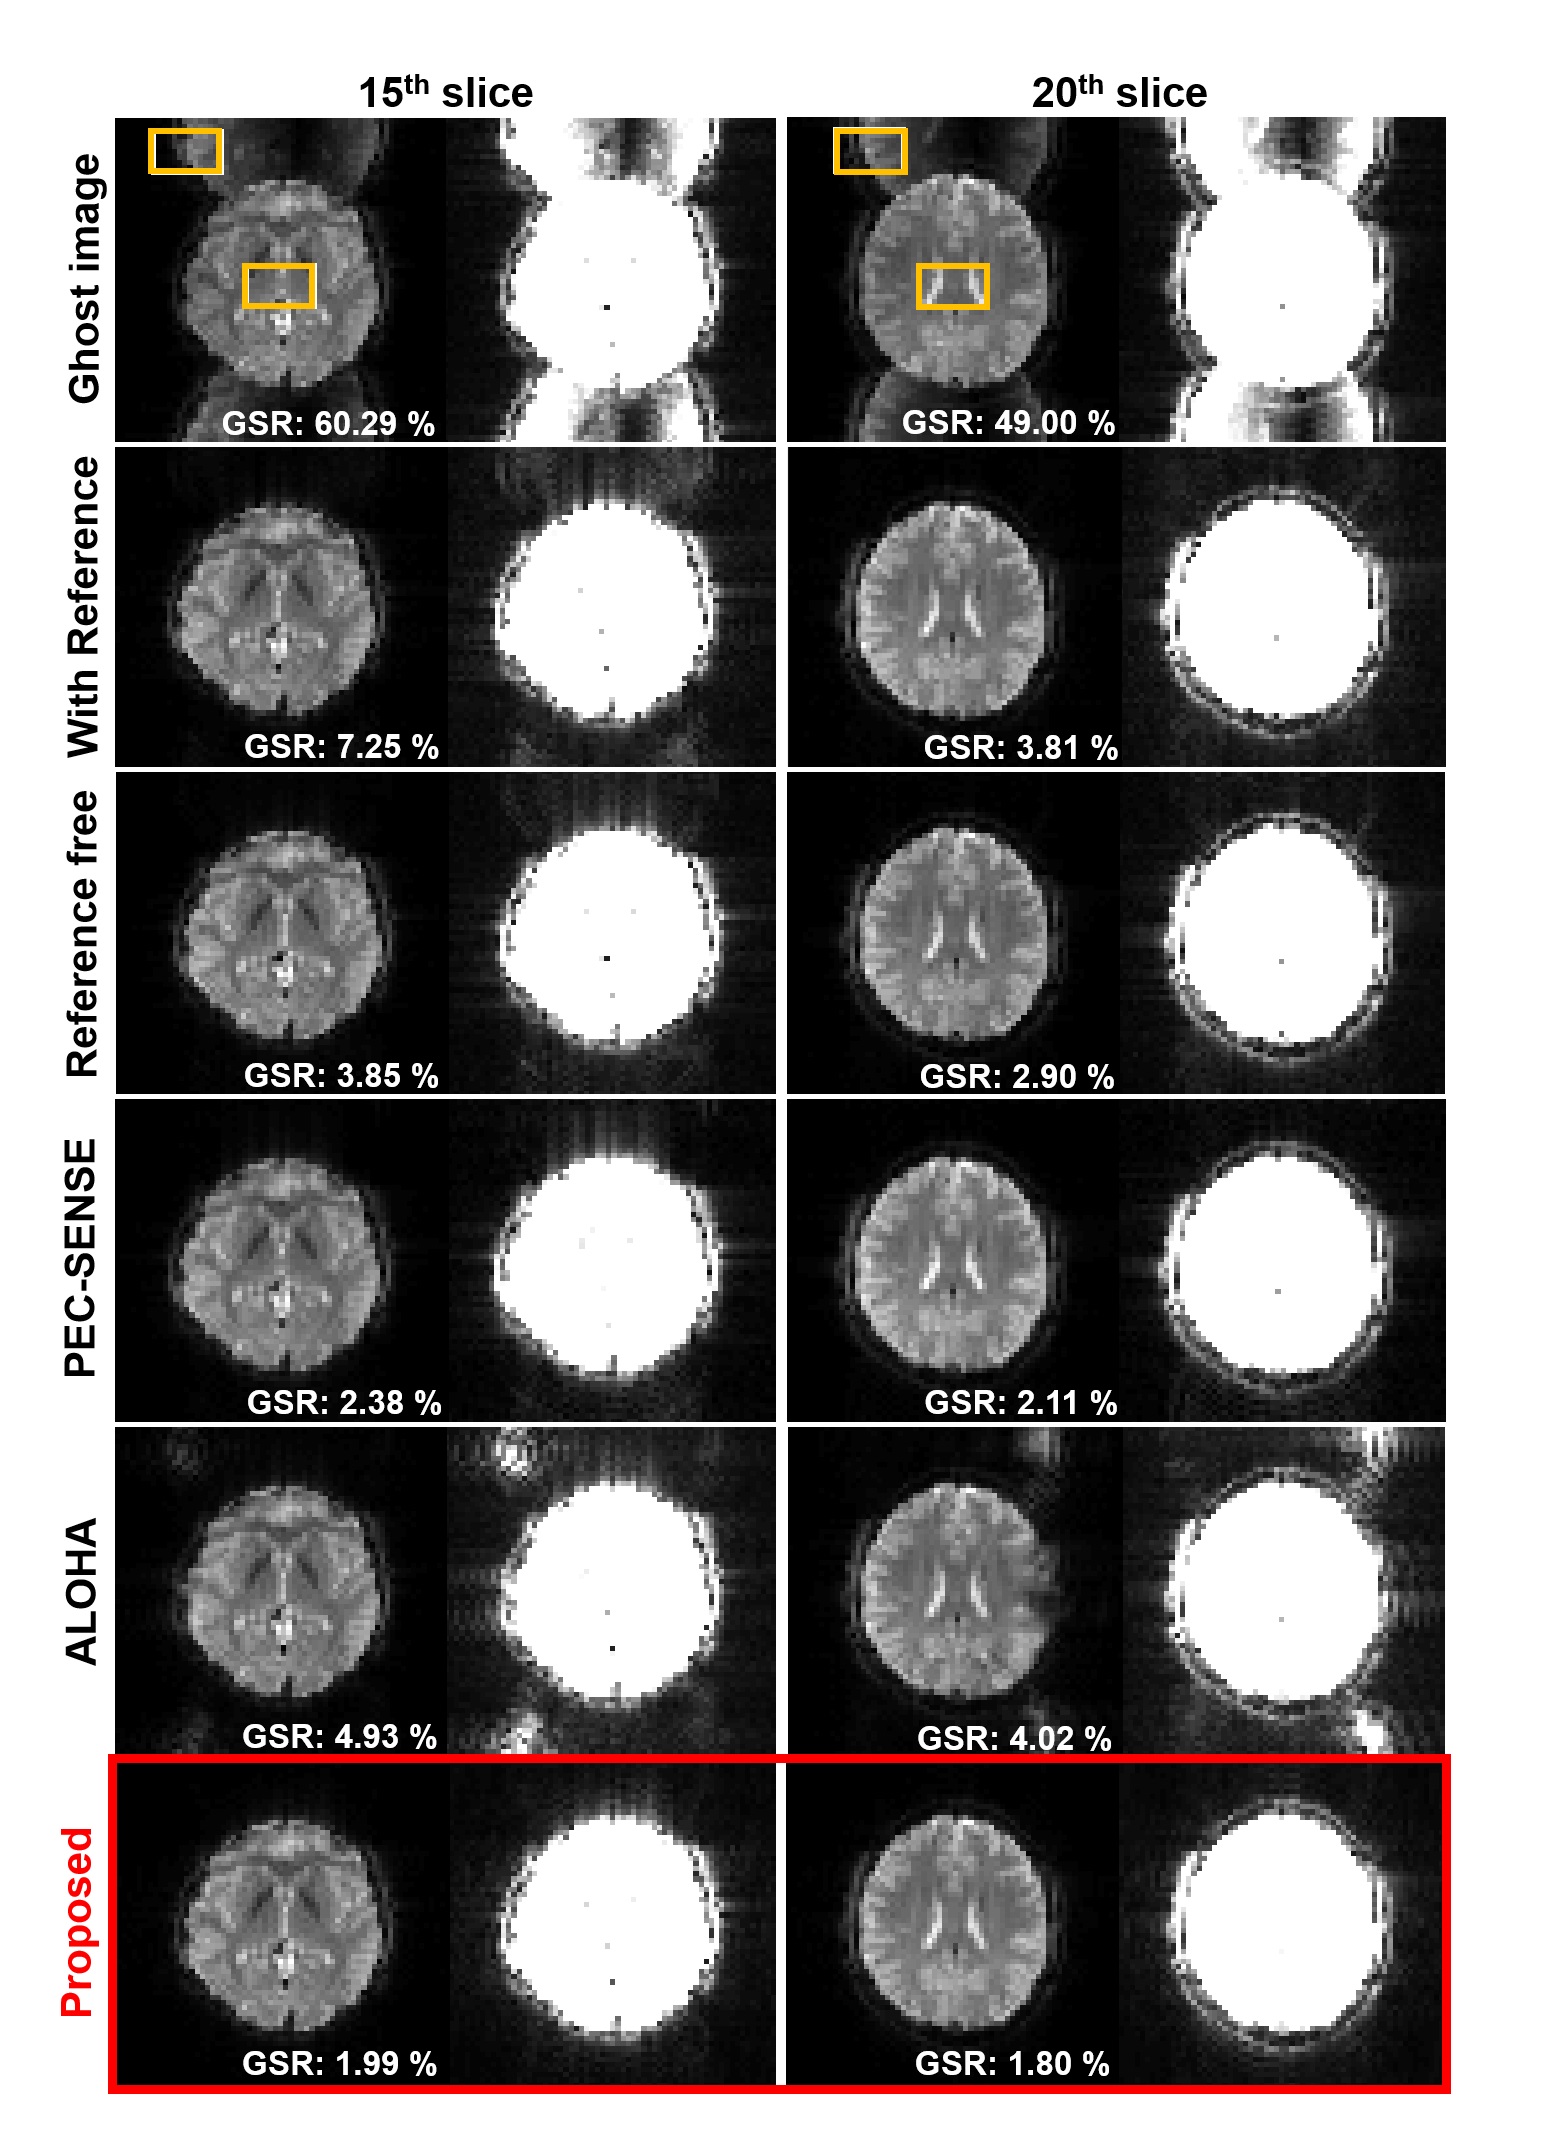

The results for 3T EPI ghost correction is shown in Fig. 5. The intensity re-scaled result images are also shown in the figure. In order to observe the remaining ghost more concisely, the image scale was re-scaled at 5 times of original intensity. The reconstruction performance of various ghost correction methods are mostly good in 3T EPI data, but slightly remaining ghost artifact can be seen in the intensity magnified images from the conventional methods. Now, Fig. 6 shows the 7T EPI ghost correction result with corresponding 5 times increase in brightness image. Most correction methods except the proposed method shows a remaining ghost artifact. Furthermore, Fig. 6 confirmed that the proposed method for accelerated EPI data (see Fig. 3(a)) can accurately correct ghost artifacts and provide visually similar results from the network in Fig. 3(b) that explicitly utilizes the GRAPPA kernel estimation steps.

To compare the result quantitatively, we calculate the ghost to signal ratio and mark ghost-to-signal ratio (GSR) value on the result figure. The GSR values corresponding to each result are calculated using regions represented by the yellow boxes and marked on the image. As shown in this result, the proposed method successfully removed ghost artifacts and shows the lowest GSR value. Although the performance of the PEC-SENSE which uses the parallel imaging information is better than the other existing methods, the GSR value was higher than the proposed method. Moreover, the proposed method using Fig. 3(a) provides much smaller GSR values than the network training using Fig. 3(b).

Figure 6: Ghost correction results of 7T GRE-EPI in vivo data by various methods. The last two rows correspond to the reconstruction by the methods using Fig. 3(a) and (b), respectively. For each slice, the 2nd column shows the intensity rescaled image of 5 times. The remaining ghost artifact is shown in other method results except the proposed method. ROI for calculating signal and ghost values are depicted by yellow rectangular.